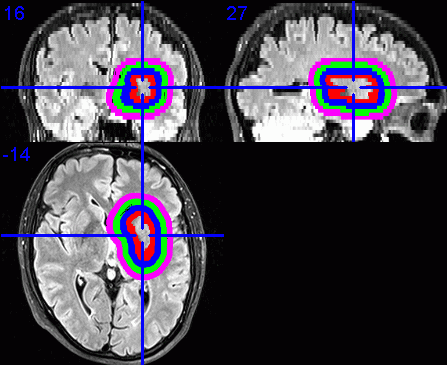

9. Visualisation of dilated VOIs

To visualise the dilated VOIs using MRIcron, I suggest first enabling the

point in section 6 above.

Load the required base images, e.g., the FLAIR images.

Select Overlay / Add. Change the Files of type: to VOIs and

-

dilated band. The VOI filenames start with a 1, 2, 3, ... depending on the

displayed in a different colour.

Click on the centre of the lesion to obtain the required view of the VOIs in

- Select File / Save as Bitmap to save this view as an image that